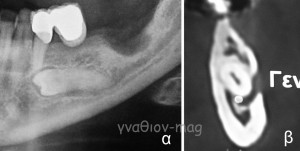

Έγκλειστος προγόμφιος και γενειακό νεύρο.

Συνήθως οι κάτω δεύτεροι έγκλειστοι προγόμφιοι όταν έρχονται σε ανατομική σχέση με το γενειακό τρήμα δεν καλύπτουν εκ ολοκλήρου τον οστικό πόρο στην περιοχή ανάδυσης του νεύρου, όπως συμβαίνει και στην περίπτωση της εικόνας 1.